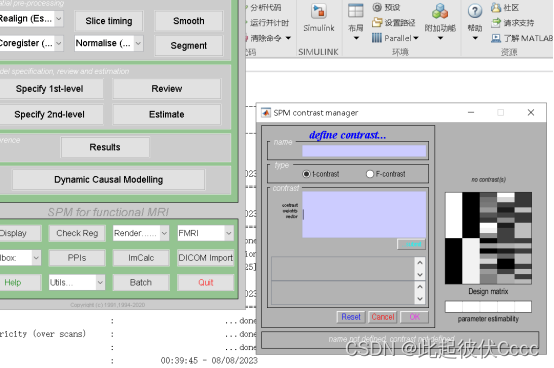

2.点击Result,点击t-contrasts按钮,然后点击Define new contrast按钮

3.输入对比矩阵名称如HC-PA,输入对比矩阵,1 -1表示第一组减去第二组,点击OK,点击Done,即添加了一组,这里添加两组,分别为HC-PA与PA-HC,如下图所示: